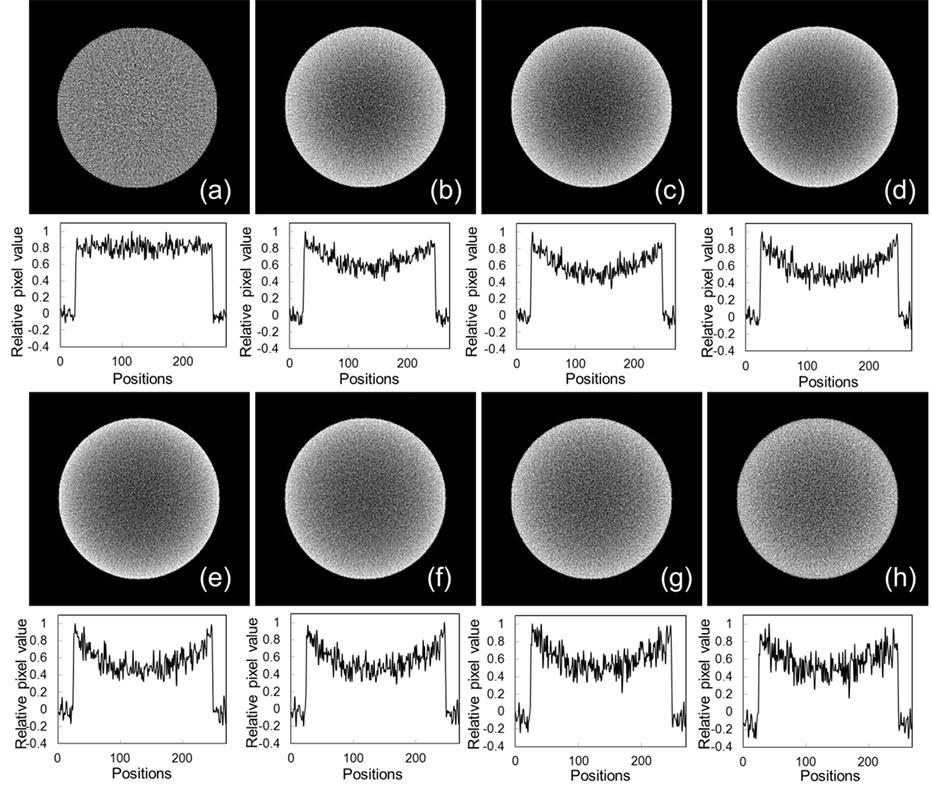

Figure 5 shows the results of the reconstructed image and the profile of the water cylinder phantom. Table 3 shows the results of the image uniformity of this phantom for different contaminating ratios of the scattered photons. Cupping artifacts appeared in the reconstructed image with scattered photons. Image uniformity was most degraded at a scattered photon contamination ratio of 40%. On the other hand, when the scattered photon contamination ratio exceeded 40%, the image uniformity slightly improved.

Figure 5. Reconstructed images and profiles of pixel values in a water cylinder phantom for each contaminating ratio of scattered photons. (a) was reconstructed by using only primary photons, and (b)-(h) were reconstructed by using scattered photons at different ratios; (b): 5%, (c): 10%, (d): 20%, (e): 40%, (f): 60%, (g): 80%, (h): 100%.

Figure 5 shows the image uniformity results. Image uniformity with scattered photons was degraded by approximately 32% from the primary photon image (Table 3). Image uniformity was most degraded (tcup: 37.7%) for images with a scattered photon ratio of 40% (Figure 5(e)). In this result, because the fractionations of the pixel values caused by the scattered photons were increased, which is shown in the profile results for each image (Figure 5), differences in the mean pixel values of each ROI between the center and edge positions became small, and therefore calculated results of the uniformity were to be slightly smaller in the classes of 40% or more contamination of the scattered photon.